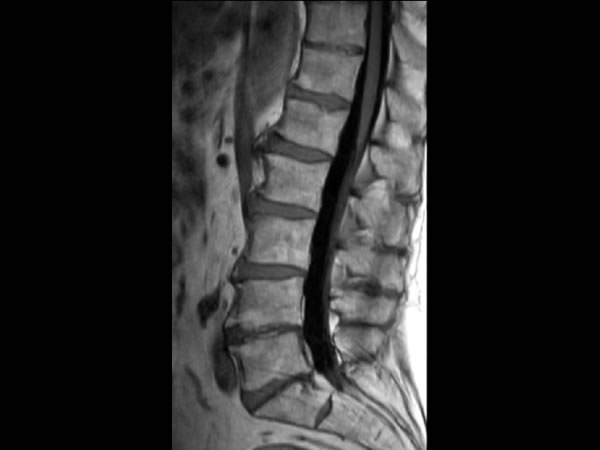

Comprehensive Lumbar Spine imaging at 3.0T